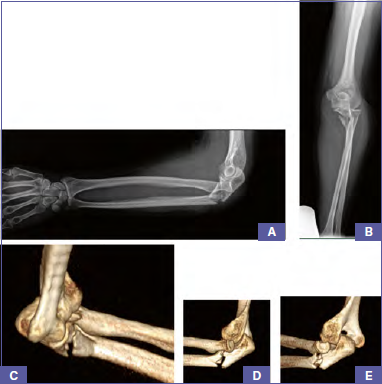

Acute management consists of immediate close reduction of radial head dislocation and immobilisation of the elbow in a long-arm cast to maintain the reduction until surgical treatment. X-ray controls were performed to confirm radial head reduction and analyse a complete view of the forearm bones. A CT scan of the injured elbow to improve planning was always performed 7 (Fig. 1).

Figure 1.A 57 years old female patient reported a Monteggia lesion with fracture of radial head (Bado IV), complicated by a coronoid fracture. Long arm X-Ray (A,B) and CT (C,D,E) in emergency room.